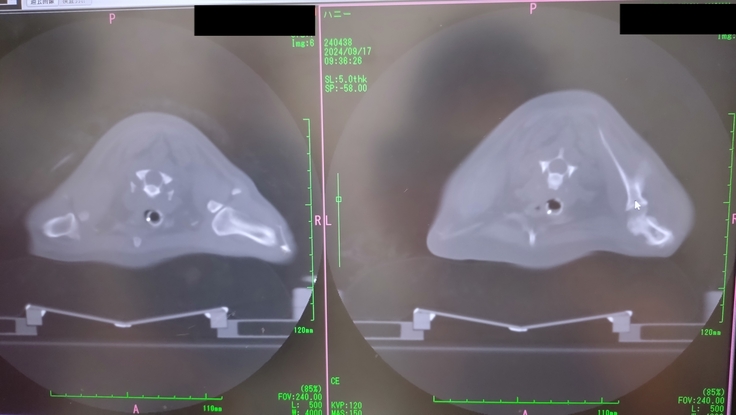

CTで、扁桃腺とリンパ節に転移した腫瘍はかなり小さくなったのが分かったけど、右前足の付け根の骨に転移が見つかってしまいました😭

この日は既に、扁桃腺とリンパ節への放射線照射は終わっていたので、午後の予約の合間で骨転移の部分の放射線照射もやっていただけることになった。全身麻酔を1日で2回もすることになりそれも心配だった。

先生からは、骨転移があるということは、全身にも回っている可能性が高い。そうなるといたちごっこでどこまで放射線をやってあげるかだと。骨転移し、状況が変わったので、今回、骨転移部分は腫瘍を小さくする目的ではなく、痛みを取るための緩和的照射のみをやりますと。今後は、痛みが治まらなかったり、痛みが出てきた所に緩和的照射を行っていきましょうと。